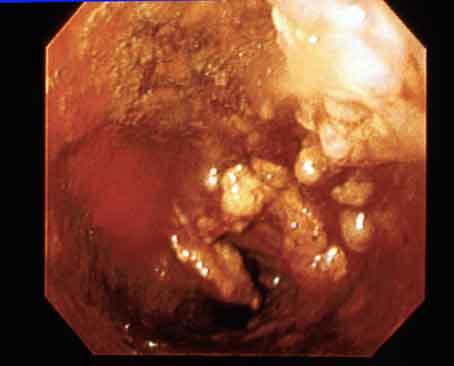

Criteria of Hist.ClassificationMalignant epithelial tumor/Undifferentiated carcinoma

LocationEsophagus/More than one of the above

Technique, MethodEndoscopy

Macroscopic TypesType 5 Unclassfied type/

Size40 -